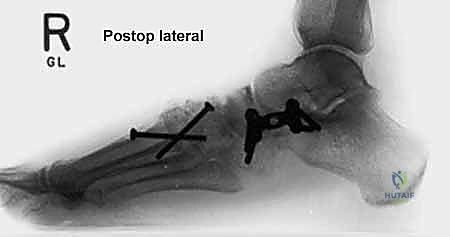

* الأشعة السينية (X-rays) مع تحمل الوزن: ضرورية لتقييم درجة انهيار القوس وزوايا العظام (مثل زاوية تالونافيكولار Meary's Angle).